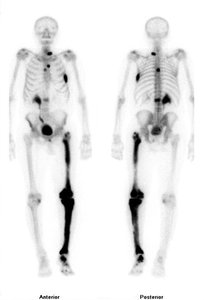

Radioactive Isotopes: Emit energy and particles; used in medical diagnostics (e.g., Tc-99 for heart and bone scans)